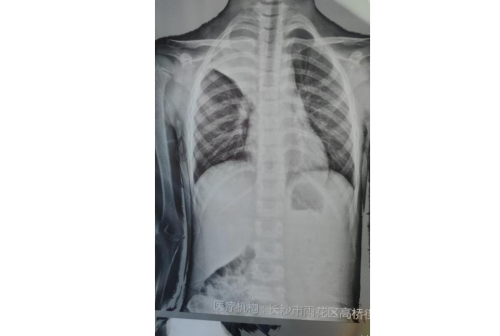

负责接诊的立博体育|实时赛事直播与比分|权威专家分析与体育竞猜平台 驻点该社区的儿科专家、副主任医师余庆乐仔细询问了病史,并做了详细的体格检查,发现患儿右肺呼吸音明显偏低,完善胸片检查后发现星星整个右上肺不张,根据经验高度怀疑为肺炎支原体肺炎,并且很有可能出现了塑形支气管炎、痰栓堵塞等肺内并发症,需要尽快转上级立博体育 住院治疗。

余庆乐一边安抚家长情绪,一边联系自己所在立博体育 的儿科,让孩子从社区尽快转诊到立博体育 。立博体育 有专人接诊,快速安排了孩子住院,当天下午就进行了纤维支气管镜检查及治疗,镜下明显看到形似“树枝”状胶冻样分泌物,肺炎支原体抗体结果回报阳性,也证实了孩子感染了肺炎支原体肺炎,经过积极对症治疗后,星星终于康复出院,王女士悬着的心也终于落地了,出院后马上找到高桥街道卫生服务中心,对余庆乐医生当面表示感谢。